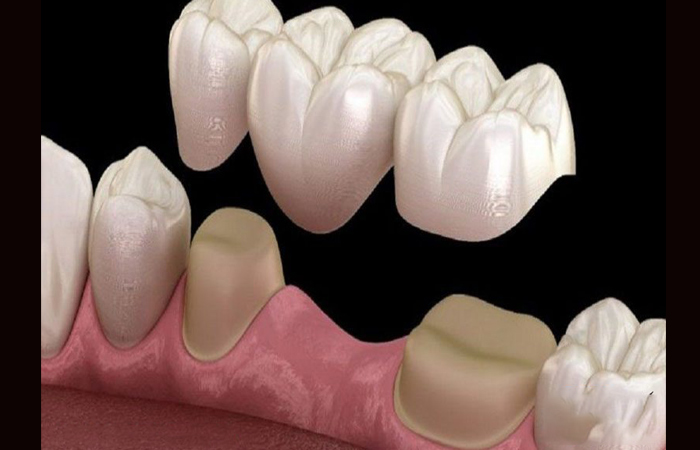

نصب بریج

پس از آماده شدن بریج، دندانپزشک آن را در محل دندانهای از دست رفته قرار میدهد.

ممکن است دندانپزشک ابتدا بریج موقت را نصب کند تا بیمار از آن استفاده کند و سپس بریج نهایی را به صورت دائمی نصب نماید.

در این مرحله، دندانهای مجاور ممکن است کمی تراشیده شوند تا پایههای محکمی برای نگه داشتن بریج فراهم شود.

در نهایت، پس از نصب، دندانپزشک اطمینان حاصل میکند که بریج به درستی

جایگزین دندانهای از دست رفته شده و از آن برای جویدن و صحبت کردن راحت میتوانید استفاده کنید.